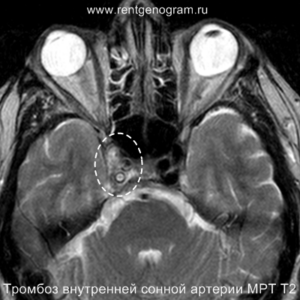

На остром этапе (Т2, Т1 и Flair могут сохранять нормальные результаты), на МРА можно обнаружить окклюзию артерии (при атеротромбоэмболическом и кардиоэмболическом механизмах), что будет выглядеть как отсутствие МР-сигнала от ведущей артерии (ВСА или СМА). Контрастное усиление на МРТ в остром этапе не приводит к накоплению контраста в области повреждения.

В течение острого этапа на МРТ и КТ выявляются все морфологические признаки ишемического инсульта. Область острого ишемического инфаркта визуализируется как зона ↑Т2, ↑Flair, ↑DWI и ↓Т1 ↓ADC. Можно обнаружить тромб в артерии. На КТ в остром этапе также чётко дифференцируется поражённая область, представляющая собой участок с потерей дифференциации мозговых структур и снижением их плотности. Контрастирование в остром периоде не показывает патологических участков с накоплением контраста.